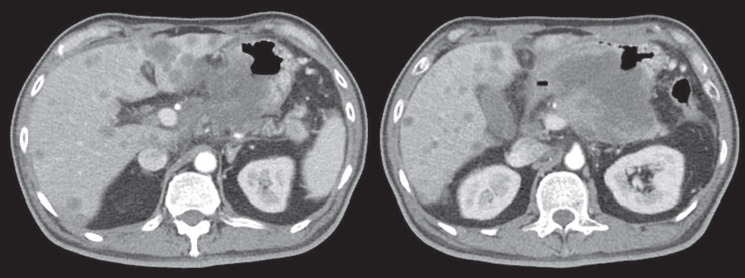

Computed tomography (CT) scan showed a huge heterogenous contrast-enhanced mass at the stomach body abutting and probably invading the duodenum and pancreas with numerous nodules in bilateral hepatic lobes and peritoneal cavity, including perigastric region (Figure 1). The picture was reasonably attributed to an advanced gastric cancer with multiple hepatic and peritoneal metastases.

Figure 1. CT scan showing a heterogenous enhanced gastric mass abutting and probably invading the duodenum and pancreas with multiple metastatic lesions in the liver.